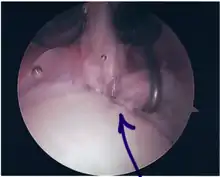

Surgical treatment of SLAP tears has become more common in recent years. The success rate for repairing isolated SLAP tears is reported between 74-94%.[7] While surgery can be performed as a traditional open procedure, an arthroscopic technique[8] is currently favored being less intrusive with low chance of iatrogenic infection.[9]

Procedure

Following inspection and determination of the extent of injury, the basic labrum repair is as follows.

- The glenoid and labrum are roughened to increase contact surface area and promote re-growth.

- Locations for the bone anchors are selected based on number and severity of tear. A severe tear involving both SLAP and Bankart lesions may require seven anchors. Simple tears may only require one.

- The glenoid is drilled for the anchor implantation.

- Anchors are inserted in the glenoid.

- The suture component of the implant is tied through the labrum and knotted such that the labrum is in tight contact with the glenoid surface.